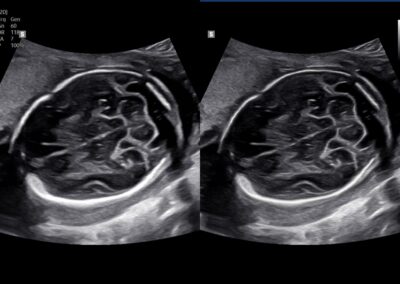

Comprehensive, advanced and expert MFM care for high-risk pregnancies

- Fetal anomalies